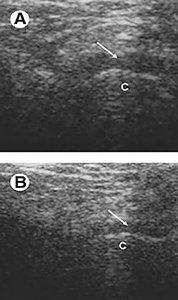

Ultrasound is useful in depicting disc displacement and effusion. Normally, the disc is situated between two hyperechoic lines represented by the mandibular condyle and the articular eminence. (Fig. 7) If the disc is displaced in the closed-mouth position, the diagnosis is disc displacement. If the disc returns to its normal position during opening, the diagnosis is disc displacement with reduction. If not, the diagnosis is disc displacement without reduction.11

FIG 7 A = open, B = closed; arrow shows disc and C is the condyle.

Regarding degenerative changes of the TMJ, ultrasound is still not recommended. One difficulty of US is the difficulty to obtain clear images, especially in the opened-mouth position, due to the overlying osseous structures. Another limitation of US is that the medial part of the disc cannot be visualized. The diagnostic value of high-resolution US is strictly dependent on the examiner's skills and the equipment used. There is a continuous need for trained and experienced professionals in this field.12